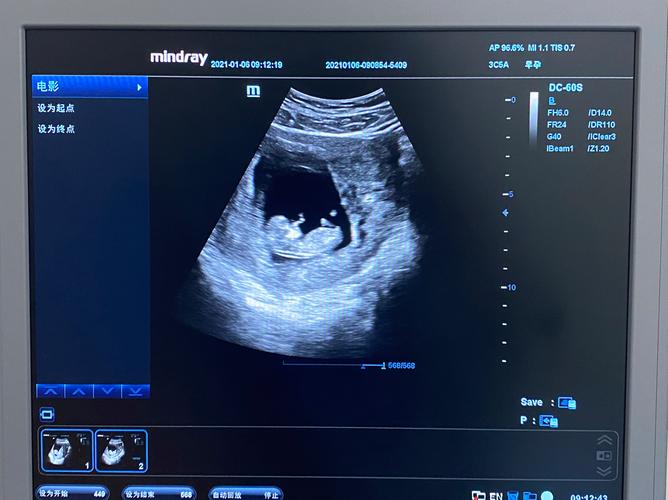

- 顶臀长(从头顶到臀部): 约 4 - 6.1 厘米。

- 心脏: 心脏已经完全发育,并且有节奏地跳动,您可以通过多普勒仪器听到它强有力的心跳声(通常在110-160次/分钟)。

- 产检安排: 通常在11-14周之间,医生会安排第一次重要的排畸检查——NT(颈项透明层)检查,结合早期的抽血结果(唐筛),可以初步评估胎儿患有唐氏综合征等染色体异常的风险,请记得提前预约。